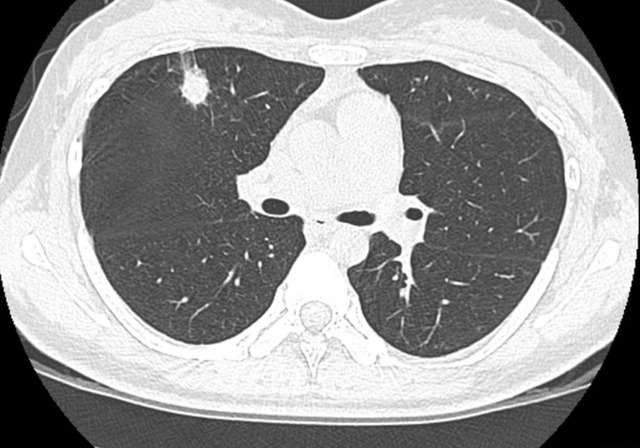

经过综合的分析和诊断,医生断定为是肺结节,建议李大叔选择保守治疗的方式,可以给他省不少的钱,如果后期病灶发展再进行手术治疗。李大叔听到自己身体有肺结节之后,非常的害怕,恐怕自己肺结节会发展成肺癌,所以回到村里之后就向大家咨询偏方。有人说经常的喝黄芪水,可以有效的帮助消散肺当中的结节,所以李大叔就购买了很多,每天都坚持泡黄芪水喝,这个习惯坚持了4年。一、51岁大叔坚持喝黄芪水,后来肺结节好了吗?最近这段时间李大叔总是觉得自己胸闷气短,于是就去医院进行检查,没想到自己的婕婕非但没有变小,还在不断的增大,会出现这种情况,就和自己天天和黄芪有关。虽然说黄芪有着补血益气清肺化痰的作用,但是作为中草药材,它并不适合天天服用,虽然黄芪可以帮助改善肺阴虚和肺气虚,但是它却对肺结节没有任何的效果。